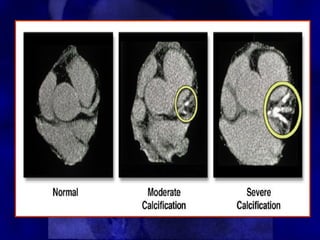

• During the early stages of coronary

During the early stages of coronary

atherosclerosis calcium starts to

accumulate within the plaque.

• As the atherosclerotic process progresses

As the atherosclerotic process progresses

the amount of calcification increases.

• During the advanced stages of

During the advanced stages of

atherosclerosis a large amount of

coronary calcification may be present.

The calcium scale is a linear scale with 4

calcium score categories:

0

0 Normal

Normal

1–99

1–99 Mild

Mild

100–400

100–400 Moderate

Moderate

>400

>400 Severe

Severe